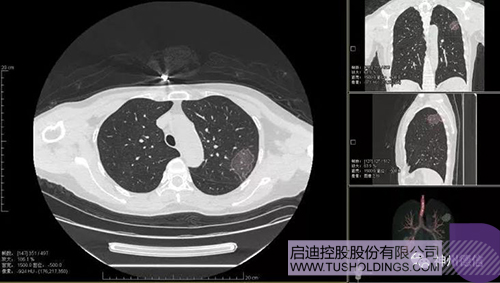

神州德信新冠肺炎检测及智能量化分析系统

启迪战略投资企业神州德信作为国内领先的肺部影像人工智能企业,针对新型冠状病毒肺炎开发了智能检测及量化分析系统,并在陕西、重庆等地定点医院投入使用。该系统在疑似病例大规模快速筛查及精准诊断方面发挥了重要作用,特别是其具有的肺炎患者临床影像跟踪量化随访功能,为快速有效阻断疫情扩散提供了有力武器。